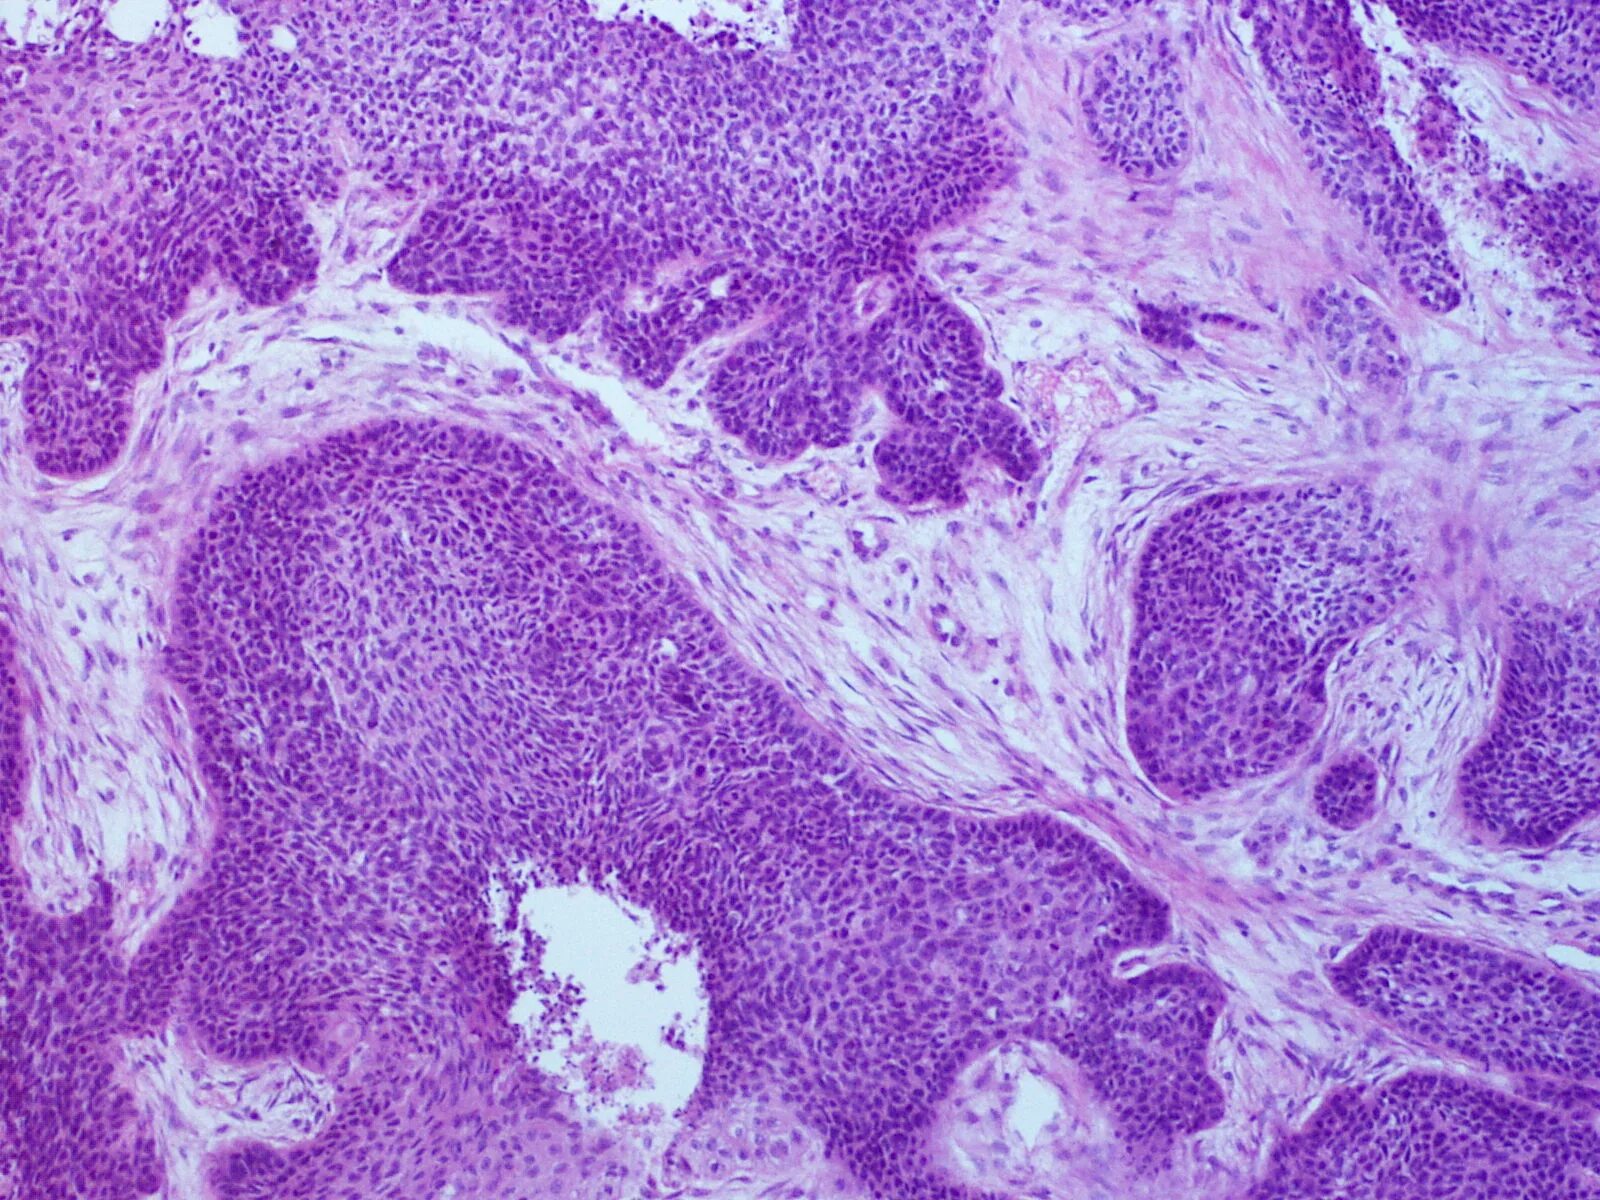

Плоскоклеточная опухоль